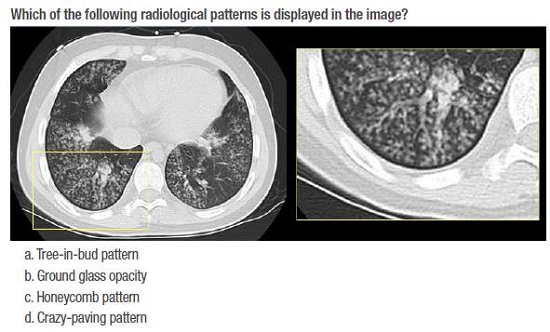

Two tests were carried out, one at the beginning and another at the end of the course. Both evaluations had 40 multiple-choice questions with one answer, which were designed based on the learning objectives proposed for the course (Figure 1).